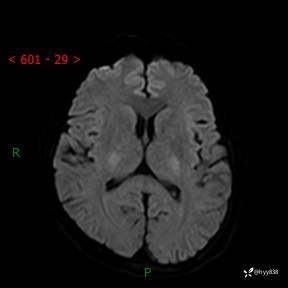

颅脑MRI平扫